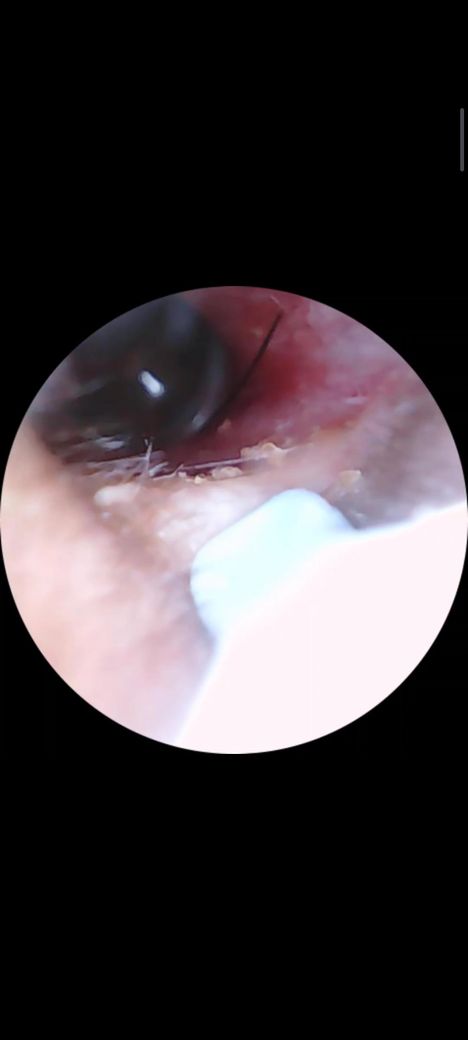

귀속에 머리카락 들어가서 안나오는데

귀내시경을 해외에서 구매하여 제고막을 봤는데

머리카락이 고막근처에 있어요 너무 깊게있어서

집에서 빼내는건 포기ㅜ 특별히 아프거나 그런건 없고 이상도없는데 그냥 둬도 되나요?

사진보고 판단 부탁드립니다.

• 1번 째 사진

불편하지 않다면 지켜보시기 바랍니다. 사진상으로 보았을때 귀 안쪽을 많이 자극한거 같으니 건드리지 마시기 바랍니다.